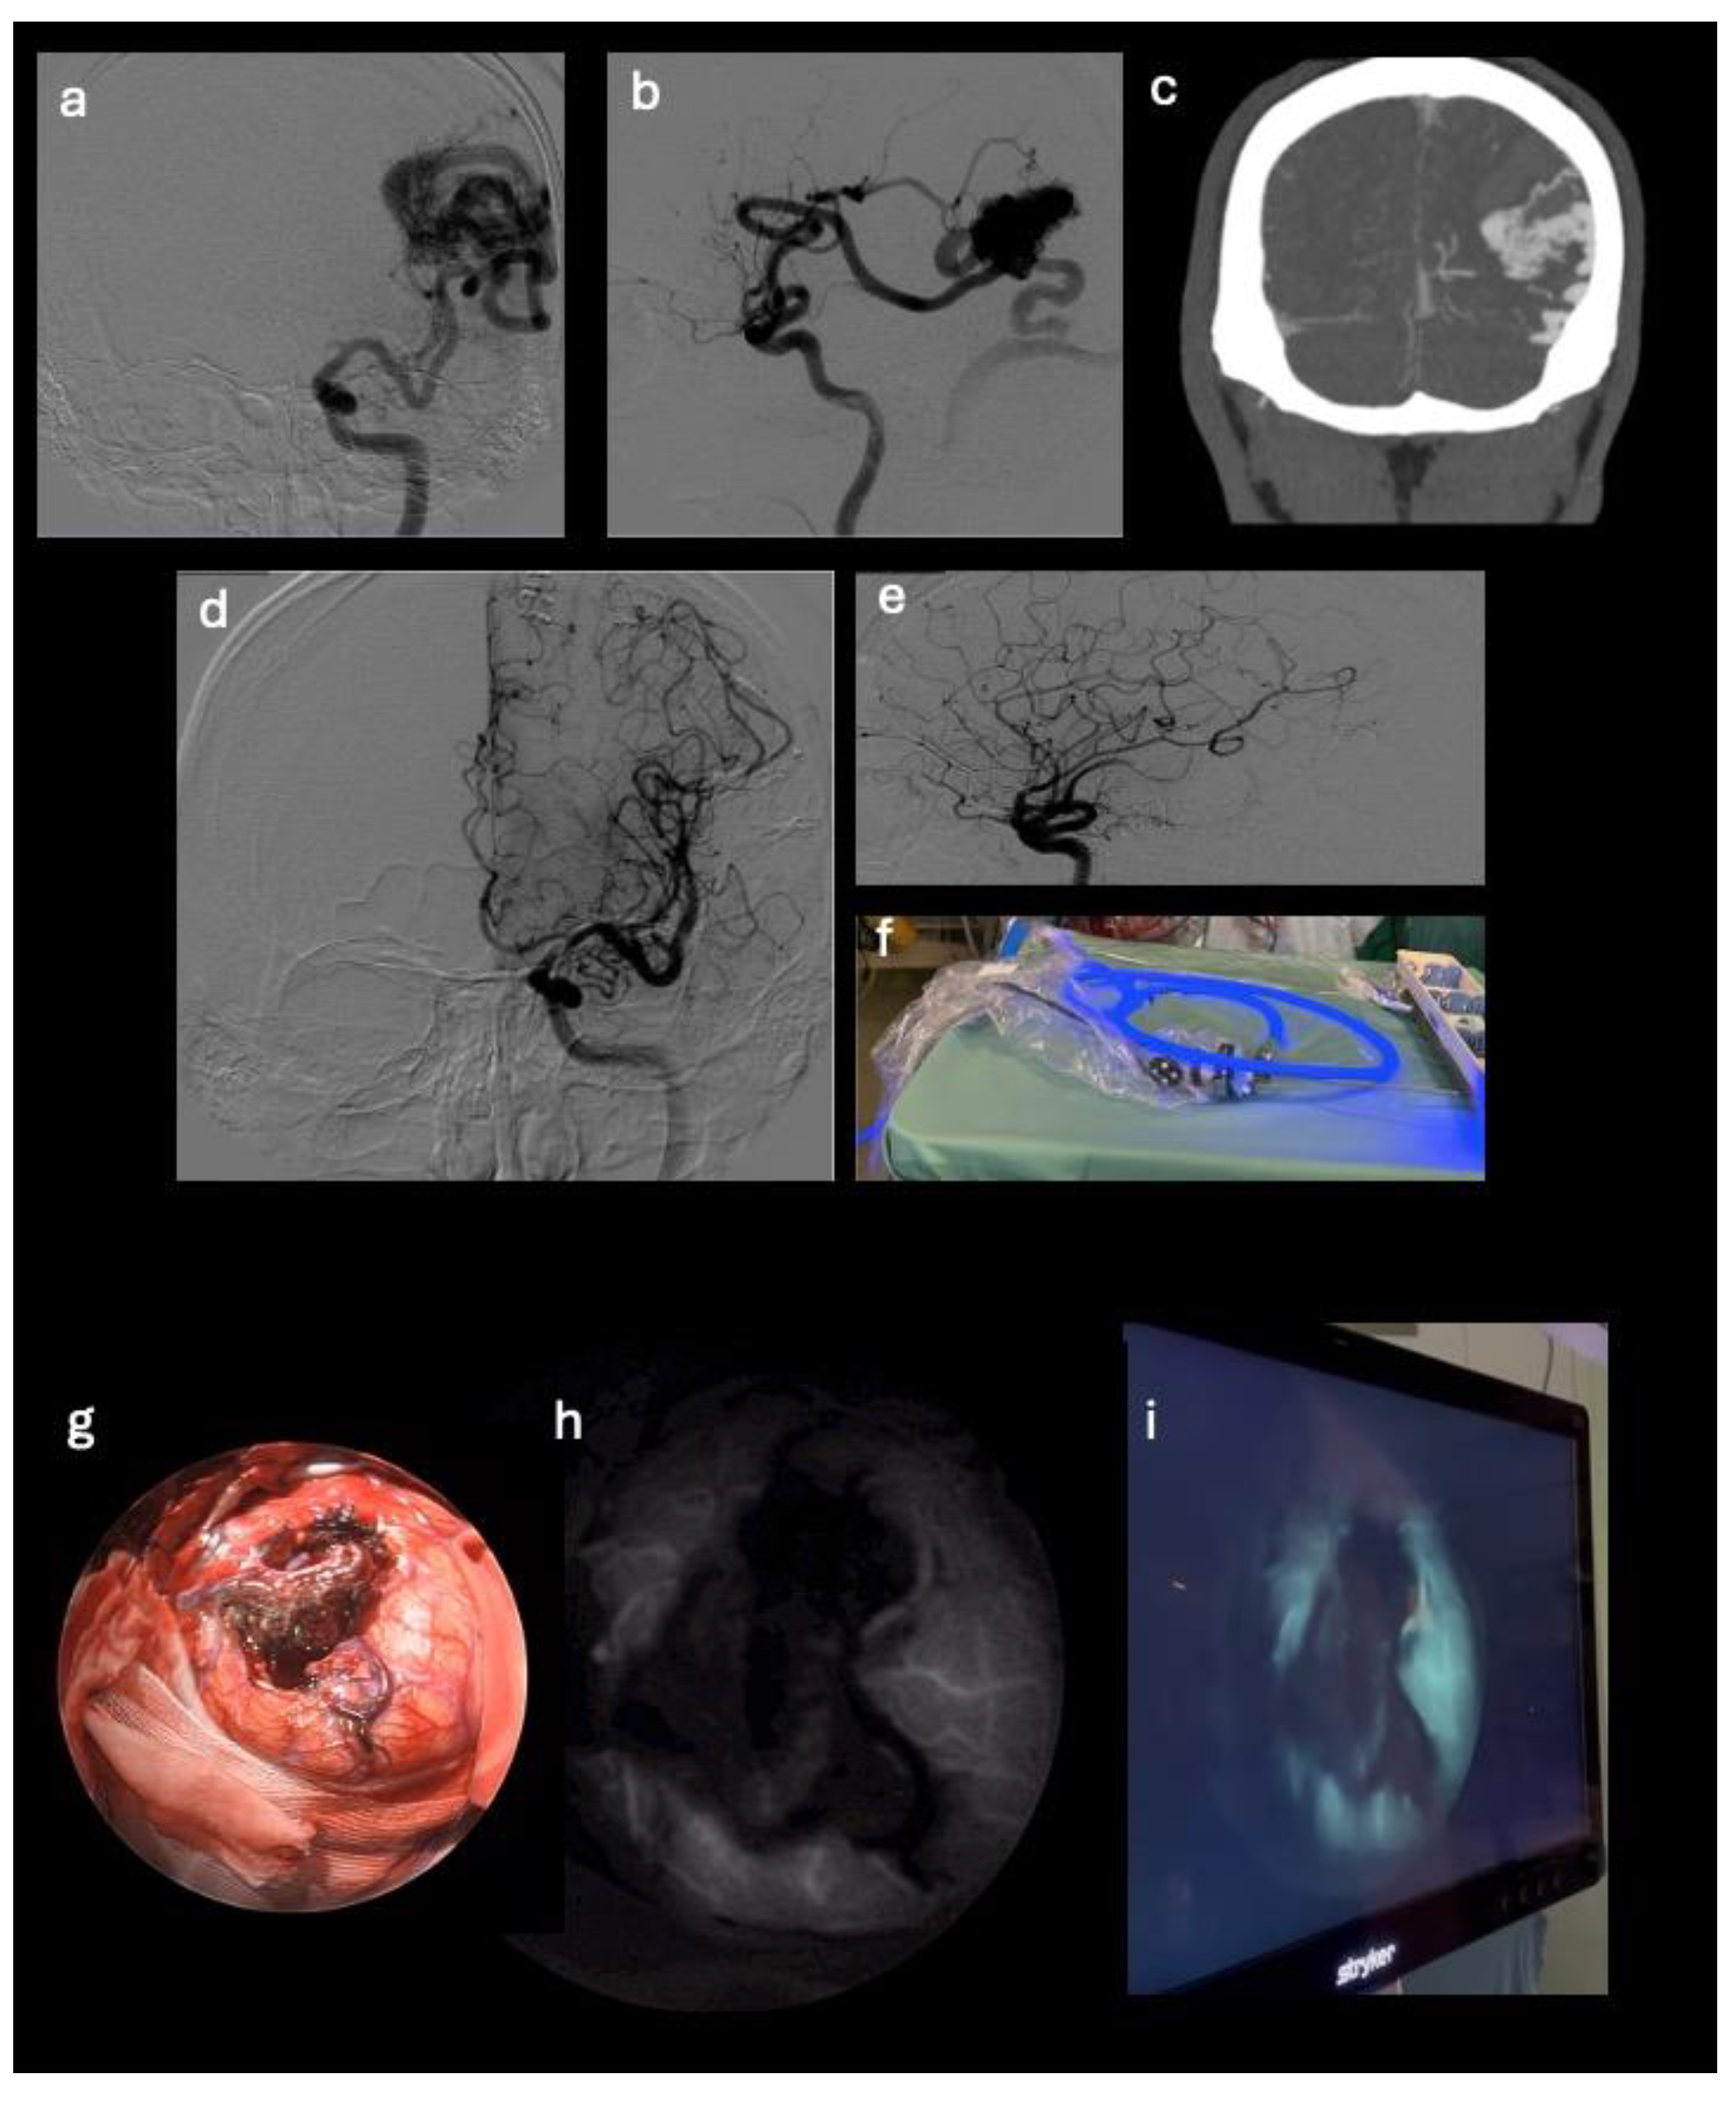

Figure 2. Pre-operative DSA and CTA images that show an AVM originating from the left middle cerebral artery and venous drainage into the ipsilateral transverse sinus (a-c). Post-operative DSA images that highlight the exclusion of the nidus (d-e). Endoscope equipment (f), standard endoscopic view (g) and endoscope in SPY mode ready for intra-operative use demonstrating the AVM exclusion (h-i).